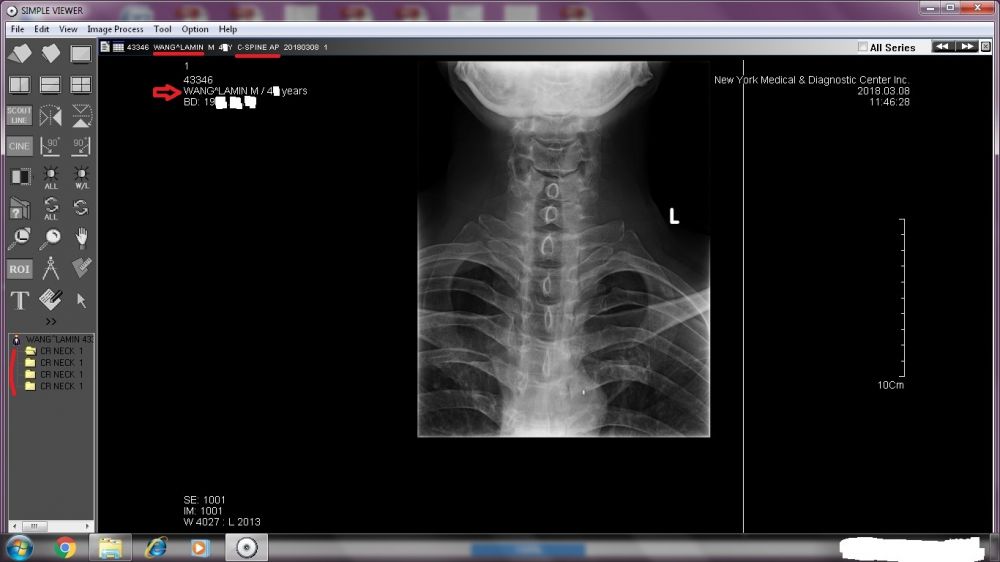

A TREMENDOUS amount needs to be revealed. Right now, I will start with the two sets of X-ray images done by New York Medical & Diagnostic Center (80-46 Kew Gardens Rd, Kew Garden, NY 11415. Tel: (718) 261-1000 ).